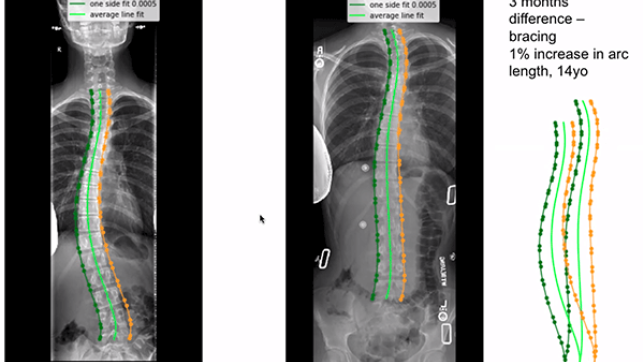

Using 20,000 Spinal Radiographs to Create Global Curvature and Alignment Parameters